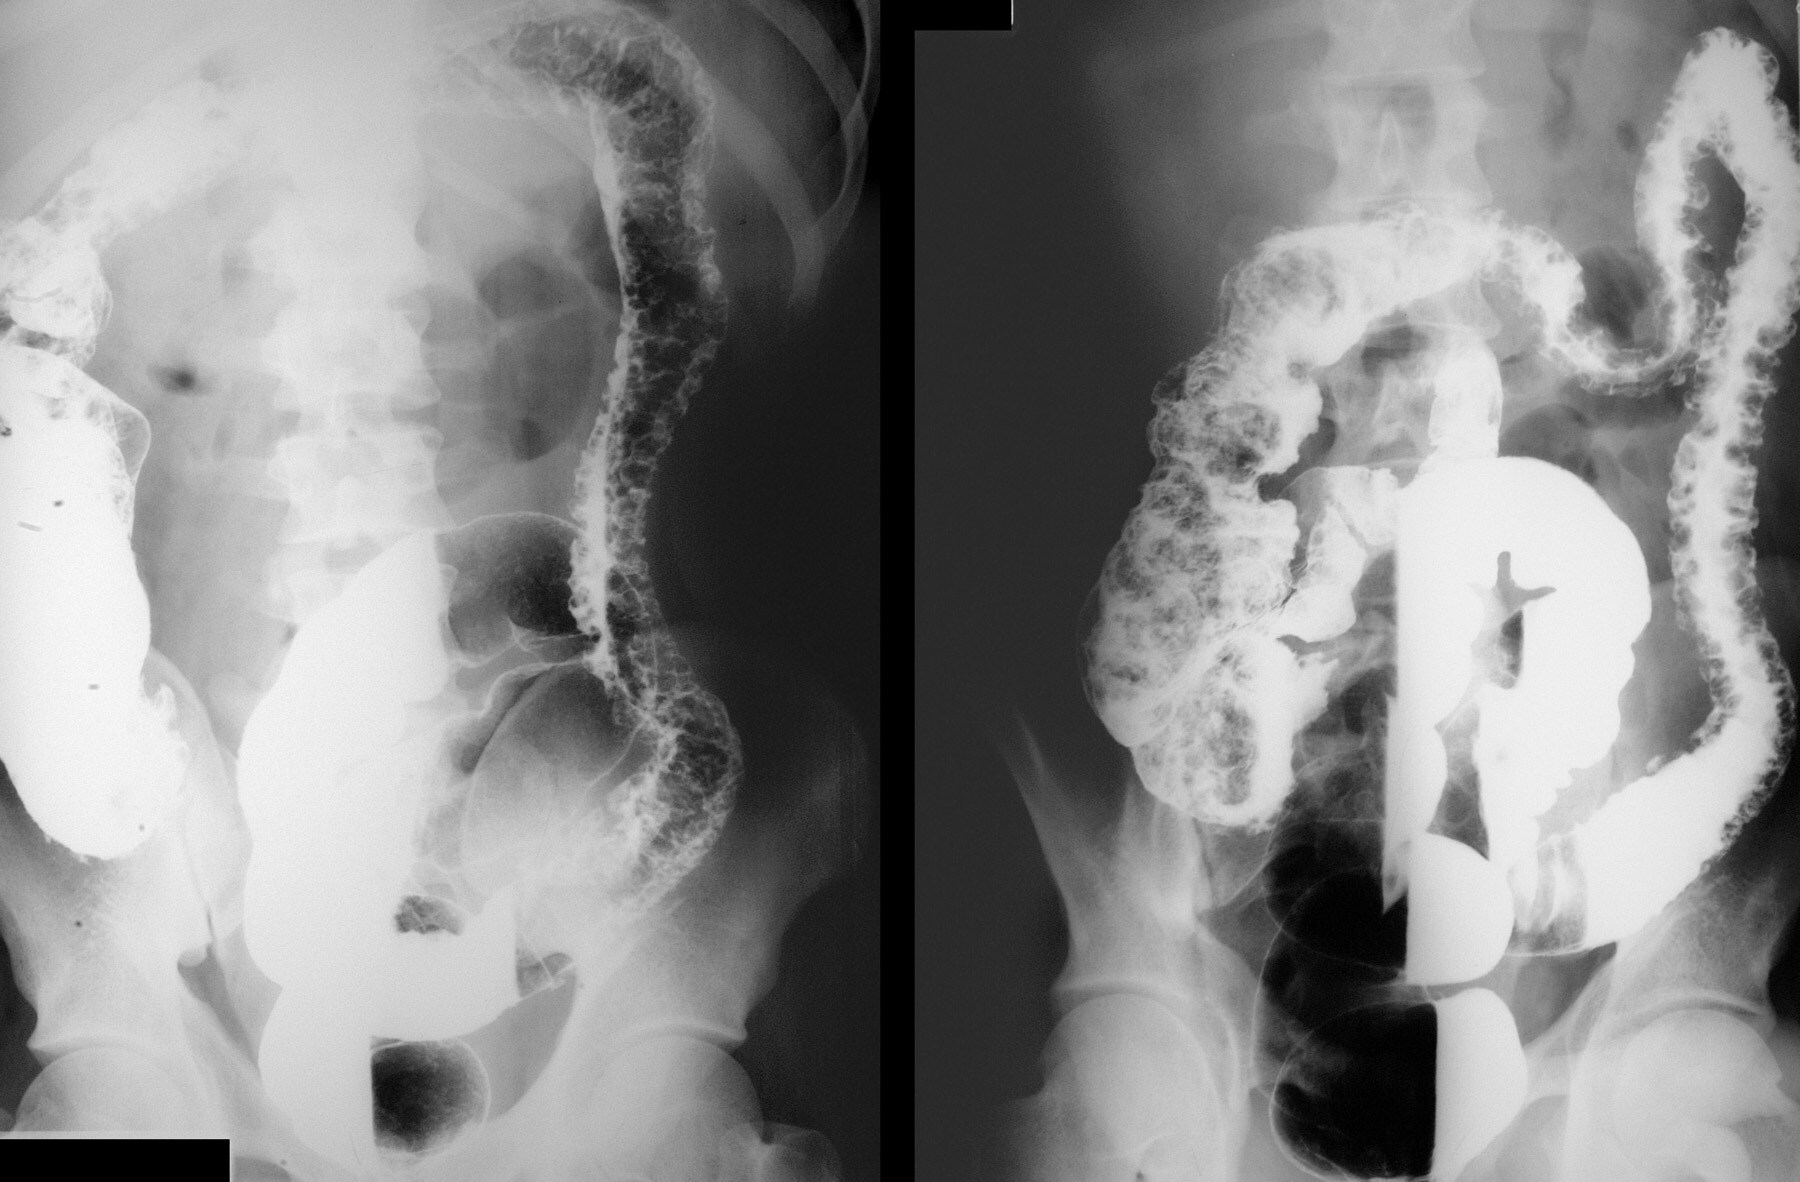

what is microscopic colitis

acute necrotizing ulcerative colitis